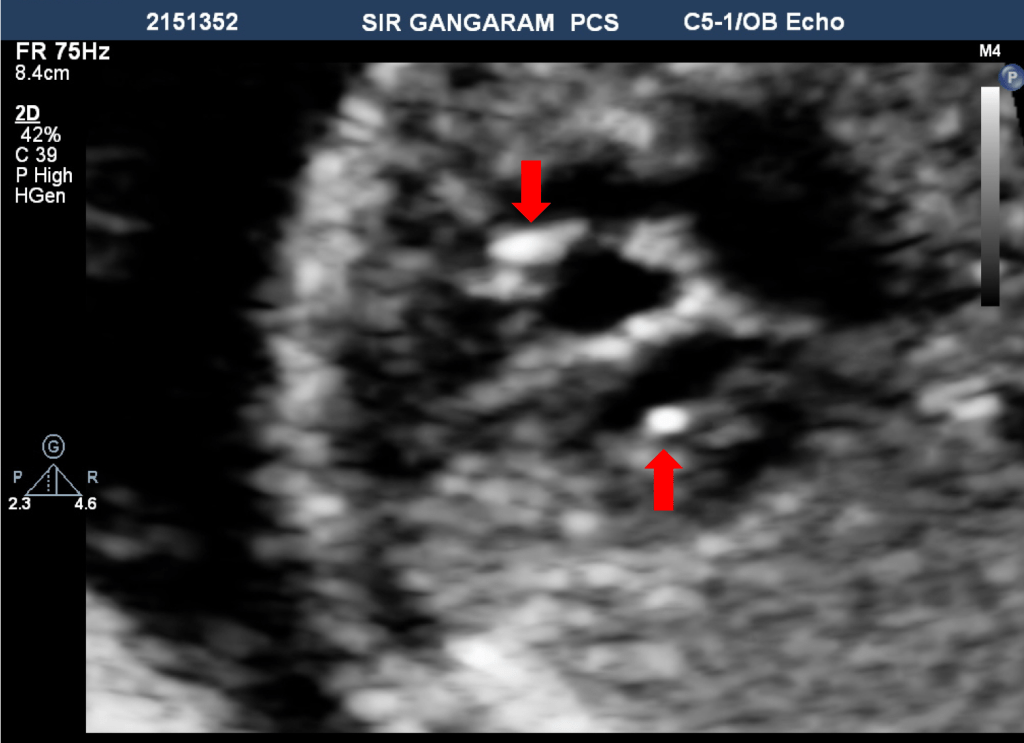

ICEF (sometimes called as Left ventricle Echogenic Focus-LVEF) is a sonographic finding of circumscribed focus that is ‘as bright as a bone,’ present in ventricle cavity, suggesting probably calcium deposition at papillary muscle or chordal attachment.

An EIF is defined as a small (<6 mm) echogenic area in either cardiac ventricle that is as bright as the surrounding bone and visualized in at least 2 separate fetal echo planes.